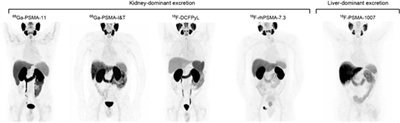

PSMA PET/CT: Hướng dẫn quy trình chung của EANM) / SNMMI đối với hình ảnh học ung thư tuyến tiền liệt phiên bản 2.0 Ngày đăng: 16/01/2026 Tại đây, chúng tôi nhằm mục đích cung cấp các hướng dẫn và tiêu chuẩn cập nhật cho việc chỉ định, thu nhận và diễn giải hình ảnh PSMA PET/CT trong ung thư tuyến tiền liệt. Các quy trình và đặc điểm...